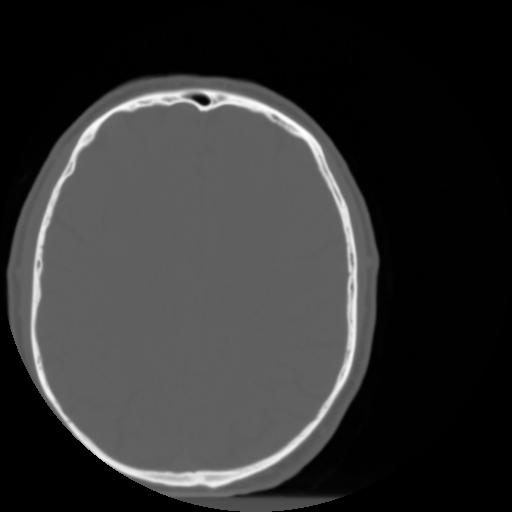

3 CEREBRO,,Axial,3.0,CEREBRO,,